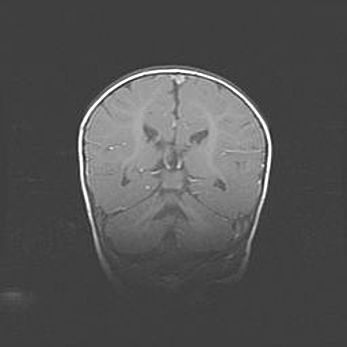

Открытая гидроцефалия.

Возраст: 6 месяцев 15 дней

Вес: 6200 г

Пол: женский

Окружность головы: 41 см

Срок гестации: 38 недель

Гидроцефалия головного мозга у новорожденных – это скопление избыточного количества цереброспинальной жидкости в головном мозге. Ее избыточное скопление в мозге приводит к патологическому расширению желудочков мозга (четырех полостей, расположенных в глубине белого вещества мозга, заполненных цереброспинальной жидкостью и связанных узкими проходами).

Открытый тип гидроцефалии (сообщающаяся) наблюдается тогда, когда нарушен механизм всасывания ликвора в системный кровоток. При этом типе причиной заболевания чаще всего является перенесенные ранее инфекции (например: менингит),  либо же наличие крови в субарахноидальном пространстве.